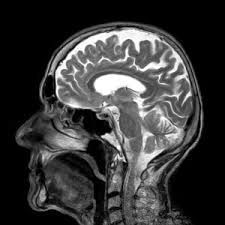

Multiple sclerosis (ms) is a relatively common acquired chronic relapsing demyelinating disease involving the central nervous system, and is the second most common cause of neurological impairment in young adults, after trauma 19. The lesions detected with mri are pathologically nonspecific. Mri is the most sensitive method for revealing asymptomatic diss … Other symptoms of ms are tingling sensations, constipation, constant fatigue, painful muscle spasms, and hearing loss. The principles of ms diagnosis are based on showing dissemination of white matter lesions in space and time. Jun 12, 2020 · multiple sclerosis (ms) is a potentially disabling disease of the brain and spinal cord (central nervous system). In ms, the immune system attacks the protective sheath (myelin) that covers nerve fibers and causes communication problems between your brain and the rest of your body. Early symptoms of ms are vision changes. Oct 10, 2019 · multiple sclerosis (ms) is an autoimmune disease that deteriorates the cover that protects the nerves (myelin sheath). The journal for your research in the following areas: Multiple sclerosis (ms) is a chronic autoimmune disorder affecting movement, ensation, and bodily functions. Jun 02, 2015 · multiple sclerosis (ms) is a degenerative disorder that affects the central nervous system, specifically the brain and the spinal cord.the disorder is characterized by destruction of the myelin, the fatty tissue that surrounds and protects the nerve fibers and promotes the transmission of nerve impulses, and damage to nerve cells. Widespread use of mri (magnetic resonance imaging) has revolutionized the ability to diagnose multiple sclerosis.

Widespread use of mri (magnetic resonance imaging) has revolutionized the ability to diagnose multiple sclerosis.